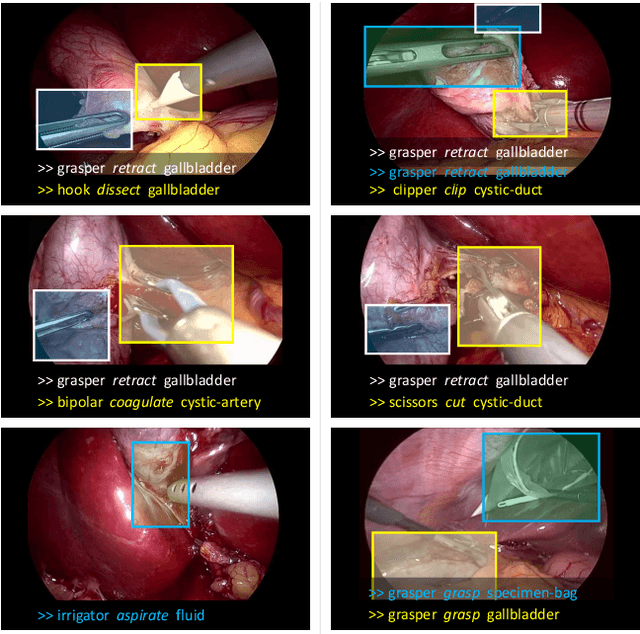

Out of all existing frameworks for surgical workflow analysis in endoscopic videos, action triplet recognition stands out as the only one aiming to provide truly fine-grained and comprehensive information on surgical activities. This information, presented as <instrument, verb, target> combinations, is highly challenging to be accurately identified. Triplet components can be difficult to recognize individually; in this task, it requires not only performing recognition simultaneously for all three triplet components, but also correctly establishing the data association between them. To achieve this task, we introduce our new model, the Rendezvous (RDV), which recognizes triplets directly from surgical videos by leveraging attention at two different levels. We first introduce a new form of spatial attention to capture individual action triplet components in a scene; called the Class Activation Guided Attention Mechanism (CAGAM). This technique focuses on the recognition of verbs and targets using activations resulting from instruments. To solve the association problem, our RDV model adds a new form of semantic attention inspired by Transformer networks. Using multiple heads of cross and self attentions, RDV is able to effectively capture relationships between instruments, verbs, and targets. We also introduce CholecT50 - a dataset of 50 endoscopic videos in which every frame has been annotated with labels from 100 triplet classes. Our proposed RDV model significantly improves the triplet prediction mAP by over 9% compared to the state-of-the-art methods on this dataset.